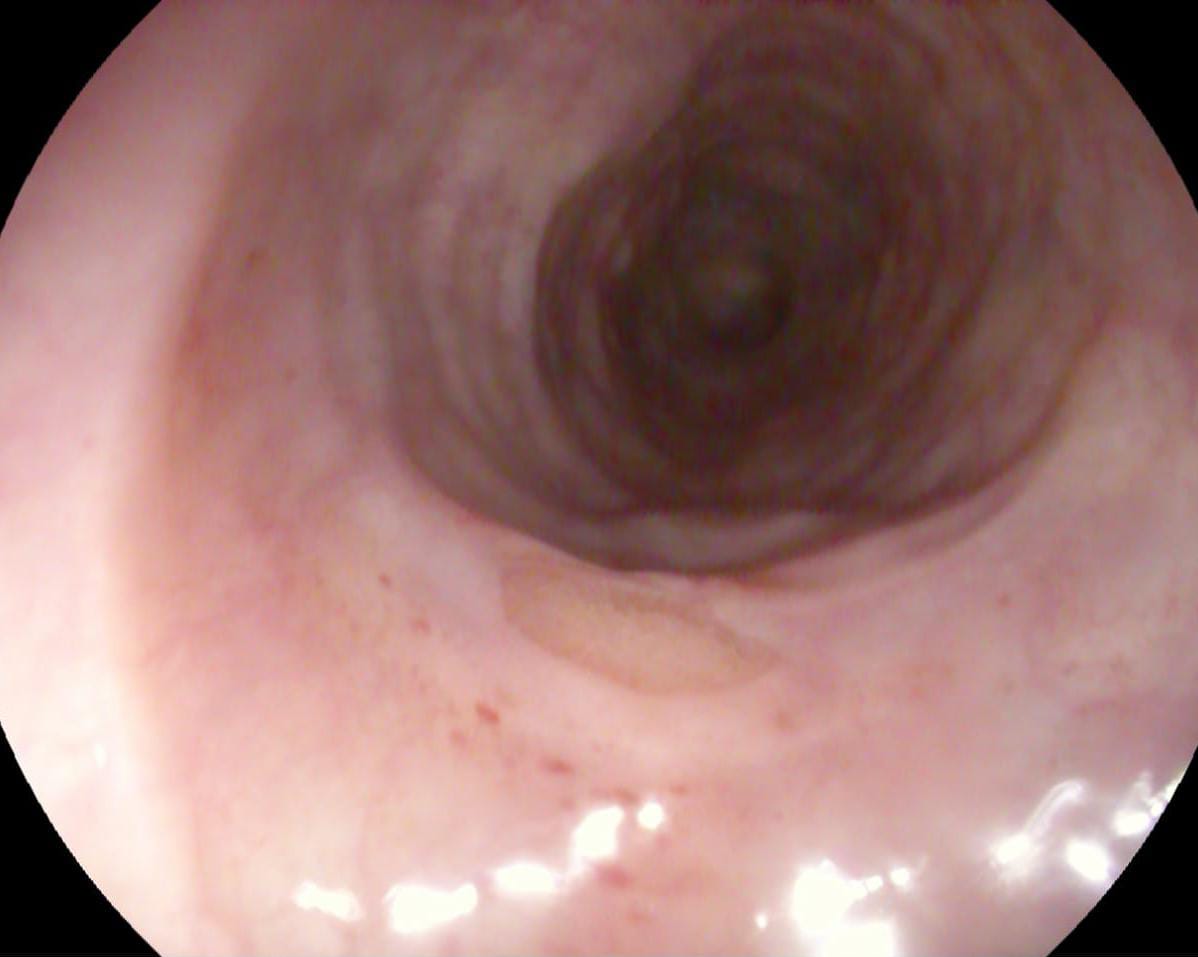

استقبل مستشفى أبو كبير المركزي حالة ثالثة لرجل مُسن يبلغ من العمر 69 عامًا بدون أسنان، أصيب بانسداد مجرى الطعام؛ نتيجة ابتلاع ليمونة كبيرة الحجم دون مضغ، حيث علقت تحت صمام المرئ السفلي، بمكان جراحة سابقة لاستئصال ورم بالمرئ.

تمكن الفريق الطبي بقسم المناظير من تفتيت الليمونة وإزاحتها لتجويف المعدة، وتم خروج الحالة بصحة جيدة.